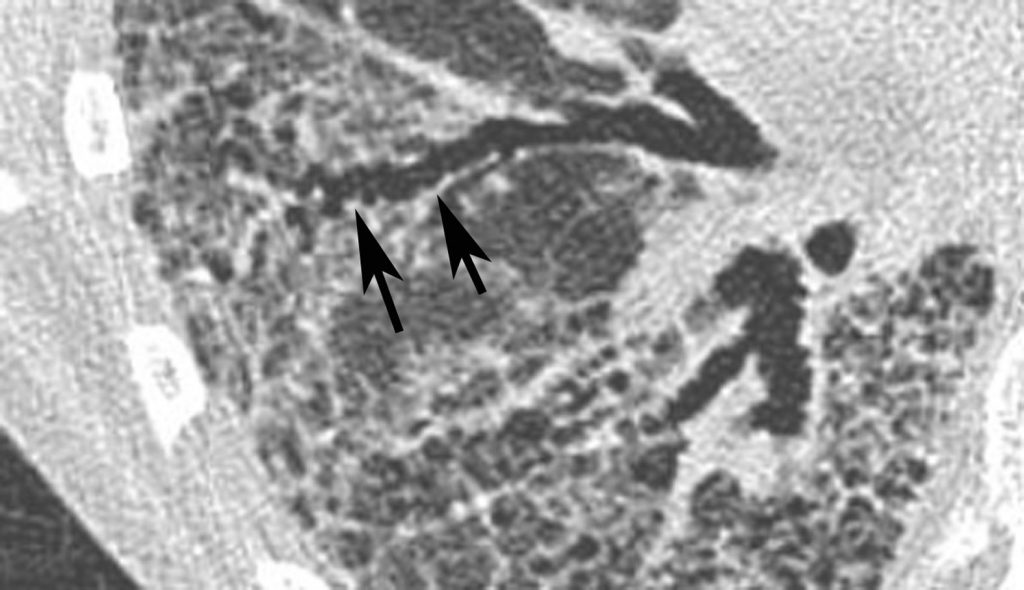

Fig. 97.6. Pneumopathie interstitielle non spécifique.

Réticulation intralobulaire. Présence de petites lignes irrégulières entrecroisées (flèches) séparant des îlots de parenchyme pulmonaire.

Source : CERF, CNEBMN, 2022.